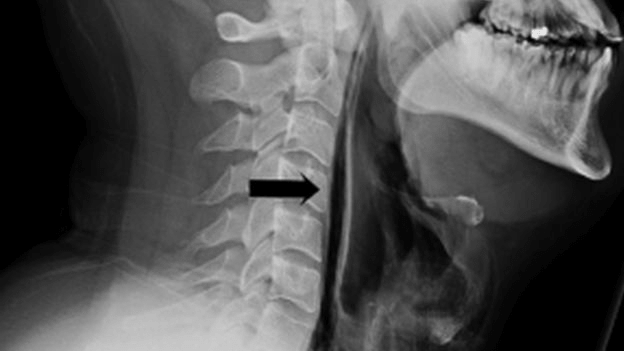

Η ακτινογραφία του ασθενή που υπέστη σοβαρή ζημιά στο λαιμό μετά από ένα συγκρατημένο φτάρνισμα.

Πρόσφατα στο Λέστερ της Βρετανίας αντιμετωπίστηκε ένα περιστατικό με 34χρονο άνδρα που υπέστη σοβαρό τραύμα στο λαιμό του και πληγή στο λάρυγγα ενώ προσπαθούσε να σταματήσει ένα δυνατό φτάρνισμα.

Χωρίς να βρίσκει διέξοδο, η πίεση διαπέρασε τον μαλακό ιστό και προκάλεσε τη σοβαρή βλάβη. Αν και οι γιατροί κρίνουν πως η σοβαρότητα του περιστατικού είναι σπάνια εκτιμούν πως όλοι πρέπει να γνωρίζουν τους κινδύνους.

Ο άντρας δήλωσε ότι αισθάνθηκε οξύ πόνο στο λαιμό του όταν συνέβη και αμέσως είχε δυσκολία να καταπιεί και να μιλήσει.

Ο ασθενής παρέμεινε διασωληνωμένος για επόμενες επτά ημέρες ώστε να δοθεί χρόνος και να κλείσει η πληγή στους ιστούς.